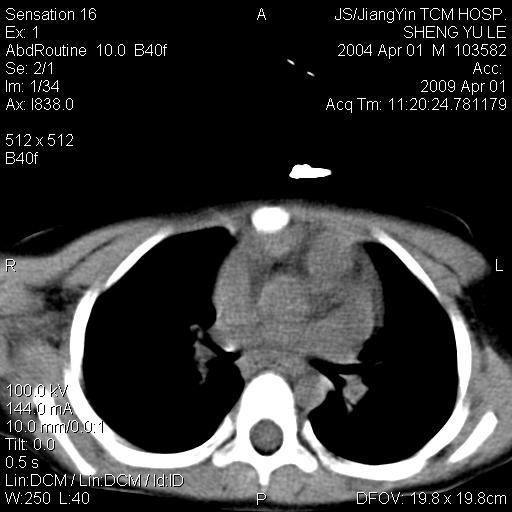

m,5岁。尿痛尿频数天。既往无病史。ct平扫腹盆腔积液。膀胱壁明显增厚。另可见心包增厚。wbc5万,骨髓穿等结果。请指教。

膀胱影像表现结合临床应该是急性膀胱炎症,但为什么有腹水呢?双肾输尿管无扩张,泌尿系压力应该不大不至于引起尿外渗,应该是腹膜感染引起的,但楼主没有提及相关症状,腹膜及膀胱结核?患者白细胞5万(结核不至于这么高啊),脾脏增大,是不是有白血病?进一步检查。。